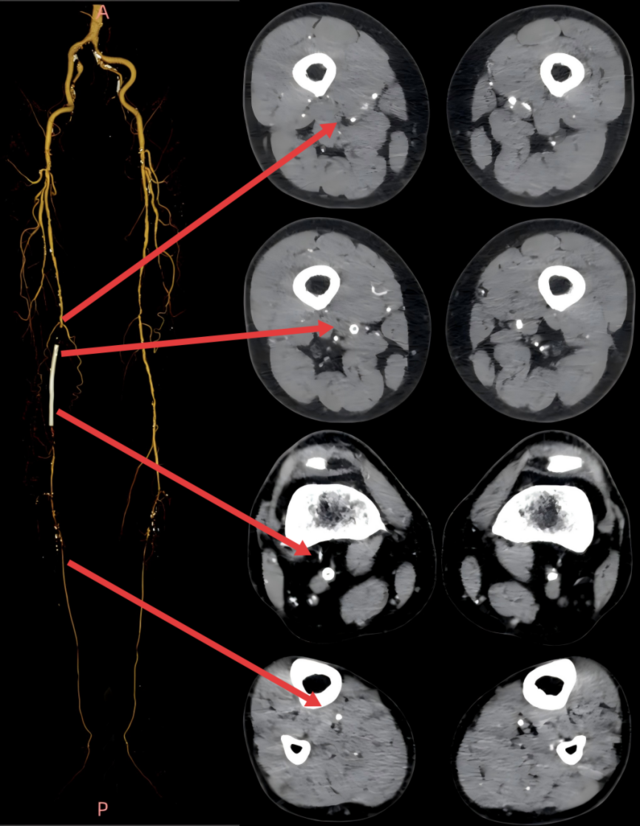

前检查更是触目惊心:下肢动脉CTA显示,李大爷右股动脉支架已完全闭塞,腘动脉还有多处重度钙化狭窄,且仅膝下胫后动脉一条 “流出道”,治疗容不得半点差错。

经过周密的术前评估(结合下肢动脉 CTA、ABI 血管功能检测)和多轮讨论后,血管外科姜坤主任团队为李大爷开展微创介入手术,全程在影像引导下精准推进:

▲术前血管造影与CTA相符

▲采用导丝通过支架内闭塞段顺利,考虑为内膜增生合并部分陈旧性血栓病变,再次造影明确病变长度。

▲血管斑块旋切系统逐段旋切抽吸病变段。

▲造影提示治疗效果良好,成功开通闭塞段。

▲Blades Up模式再次抽吸病变段,股腘动脉管腔获得满意,膝下胫后动脉、足部血流灌注同前,未见明显栓塞。

▲股浅、腘、胫后动脉经POBA+5*300 先瑞达DCB球囊扩张。

▲治疗完毕,最终造影结果,股浅动脉局部非限流性夹层,支架内、膝下流出道血流速满意。